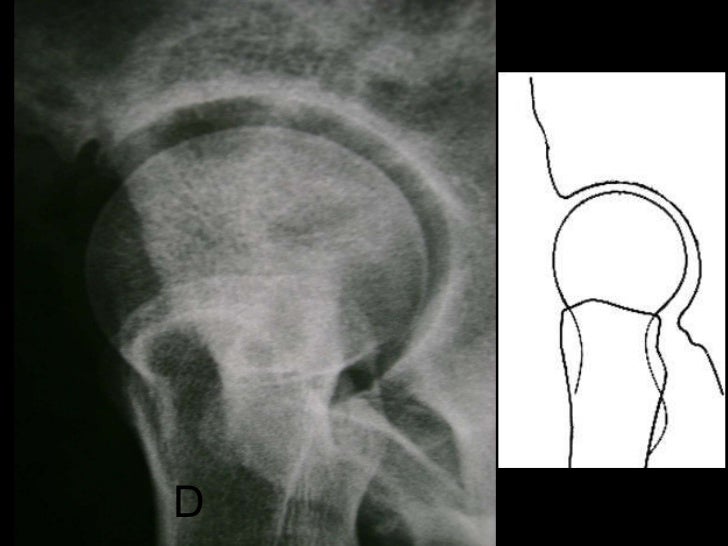

<ul><li>Em uma incidência de lequesne, podemos observar uma possível impactação entre a cabeça do fêmur e a região do acet...

D

26. 27. <ul><li>Em uma incidência de lequesne, podemos observar uma possível impactação entre a cabeça do fêmur e a região do acetábulo, diminuição do espaço articular e a cobertura do acetábulo. </li></ul>

27. 28. D